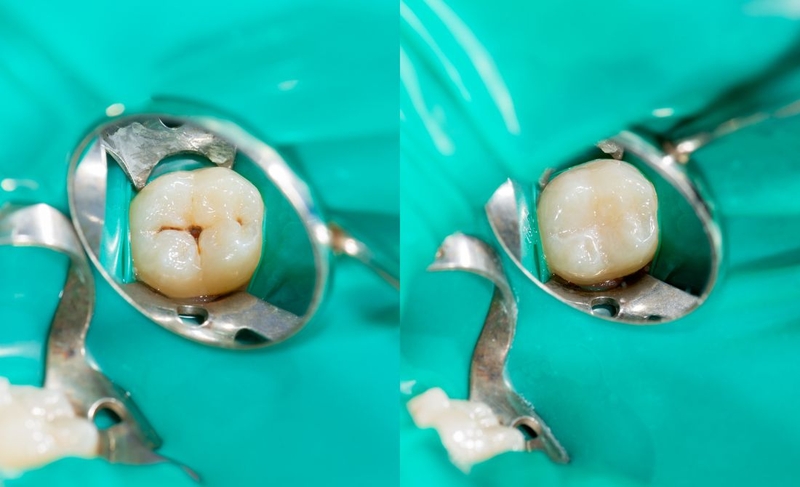

Chất hàn răng composite là loại vật liệu được sử dụng phổ biến nhất nhờ tính thẩm mỹ cao. Composite có màu sắc tự nhiên, dễ dàng điều chỉnh để phù hợp với màu răng thật, giúp vết trám trở nên kín đáo và hài hòa. Ngoài ra, composite còn có độ bền tương đối cao và dễ dàng thao tác. Tuy nhiên, một nhược điểm của composite là có thể bị đổi màu sau một thời gian sử dụng, đặc biệt khi tiếp xúc với các chất có màu như cà phê, trà, rượu vang.